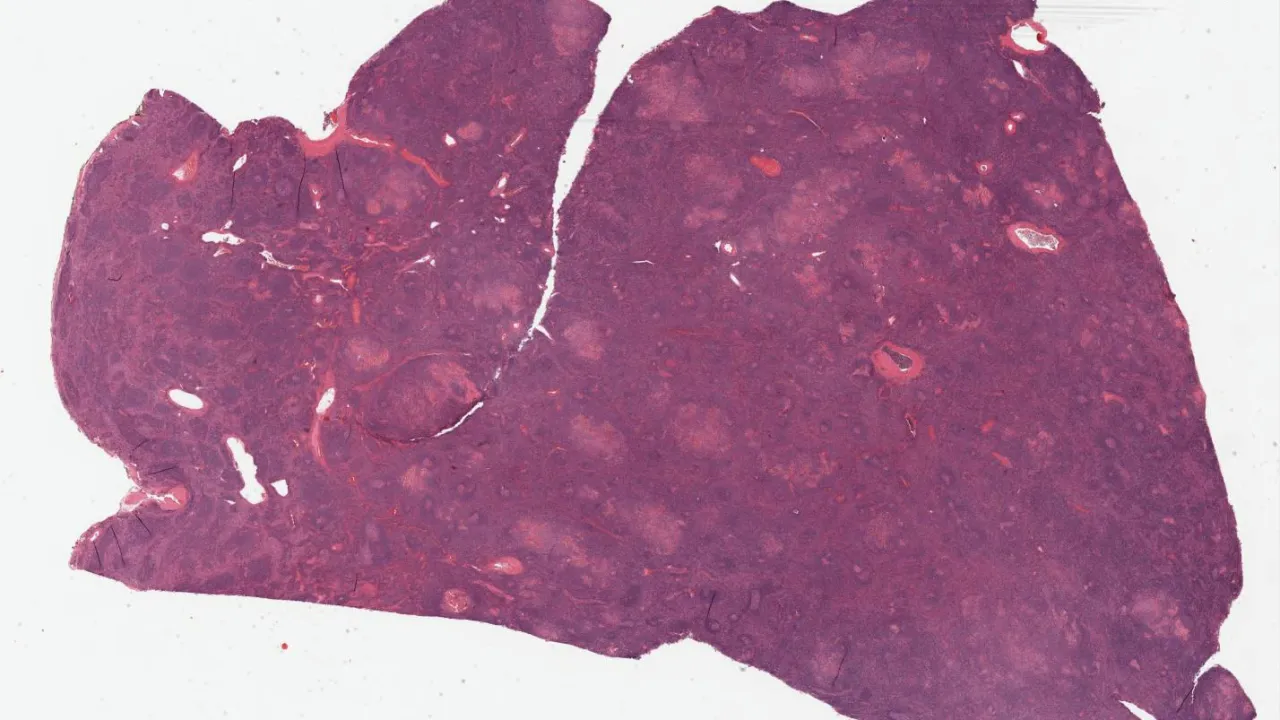

Spleen, Littoral cell angioma